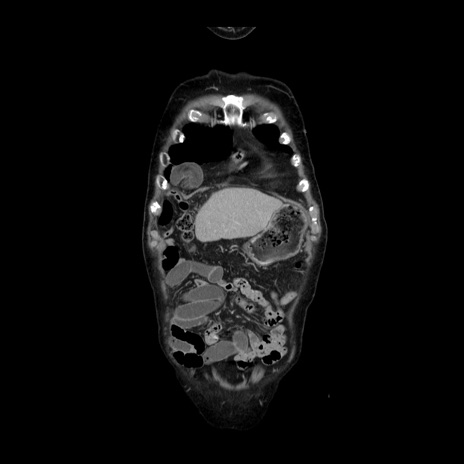

横断像

【症例】70歳代男性

【主訴】腹痛

【現病歴】肝硬変・肝細胞癌にてかかりつけの方。約9時間前に食後より腹痛出現。症状が徐々に増悪し、嘔吐出現したため来院。

【既往歴】肝硬変、肝細胞癌(RFA、TACE後)

【身体所見】意識清明、表情苦悶様、BT 36℃、BP 129/78mmHg、P 88bpm、SpO2 97%(RA)、右上腹部から心窩部にかけて圧痛あり、反跳痛なし、筋性防御あり。

【データ】WBC 5800、CRP 0.16